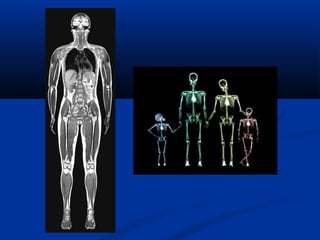

Examination Typical effectivedose (mSv) (milli rem) Chest X-ray 0.1 10 Head CT 1.5 150 Screening mammography 3 300 Abdomen CT 5.3 530 Chest CT 5.8 580 Chest, Abdomen and Pelvis CT 9.9 990 CT colonography (virtual colonoscopy) 3.6 - 8.8 360 - 880 Cardiac CT angiogram 6.7-13 670 - 1300 Barium enema 15 1500 Neonatal abdominal CT 20 2000